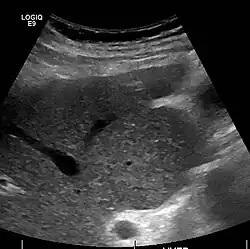

Caudate lobe hypertrophy on ultrasound due to cirrhosis

Ultrasound is routinely used in the evaluation of cirrhosis.[45] It may show a small and shrunken liver in advanced disease. On ultrasound, there is increased echogenicity with irregular appearing areas.[64] Other suggestive findings are an enlarged caudate lobe, liver surface nodularity[65] widening of the fissures and enlargement of the spleen.[66] An enlarged spleen, which normally measures less than 11–12 cm (4.3–4.7 in) in adults, may suggest underlying portal hypertension.[67] Ultrasound may also screen for hepatocellular carcinoma and portal hypertension.[45] This is done by assessing flow in the hepatic vein.[68] An increased portal vein pulsatility may be seen. However, this may be a sign of elevated right atrial pressure.[69] Portal vein pulsatility is usually measured by a pulsatility index (PI).[68] A number above a certain value indicates cirrhosis (see table below).

Portable ultrasound is a low-cost tool to identify the sign of liver surface nodularity with good diagnostic accuracy.[65]